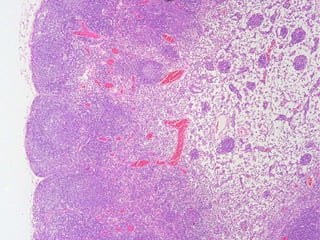

Primario: De aspecto homogeneo y no activo en la respuesta inmunologica.

Secundario: se identifican dos zonas.

1. Una zona externa periferica oscura (corteza o manto), que contiene

Corteza

Centro germinal

Muestra tres zonas: oscura, basal clara y apical clara. La zona

oscura posee centroblastos (celulas B que no poseen

inmunoglobulinas de superficie), migran a la zona basal clara, expresan

inmunoglobulinas de superficie y se conocen como centrocitos. Las

celulas que no sintetizan las inmunoglobulinas de superficie se fuerzan

a apoptosis y son destruidas por macrofagos.

Los centrocitos migran a la zona apical

clara y se tornan celulas B de memoria

Centro Germinativo